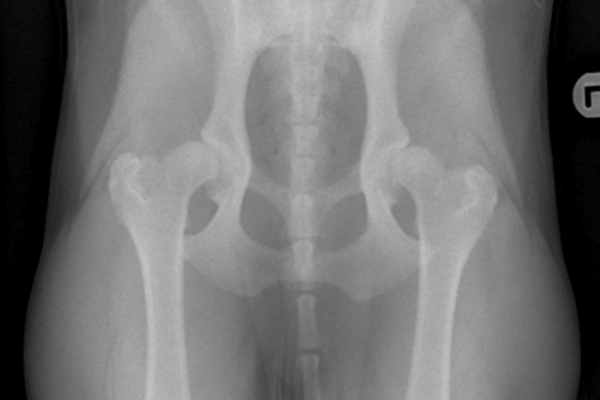

As a puppy, labrador retriever Bruce was always to run about and play. But Bruce's owner, Julie a registered head veterinary nurse from Warrington knew from an early age that Bruce had issues with hind legs. "Bruce always had 'clicky' hips and I was suspicious that there was a problem from when he was young puppy'. Bruce was first x-rayed at 6 months of age and Julie's vet, Dr. Iain Mottram from Warrington Vets4Pets noticed the hip abnormalities straight away. "Bruce's hip joints had not developed properly and the result was that the joints would 'slip' in and out of position - this condition is very painful" Dr. Mottram explains.

Bruce had further x-rays taken under anaesthetic so that his pelvis and femur could be very accurately measured for the implants that would be needed.